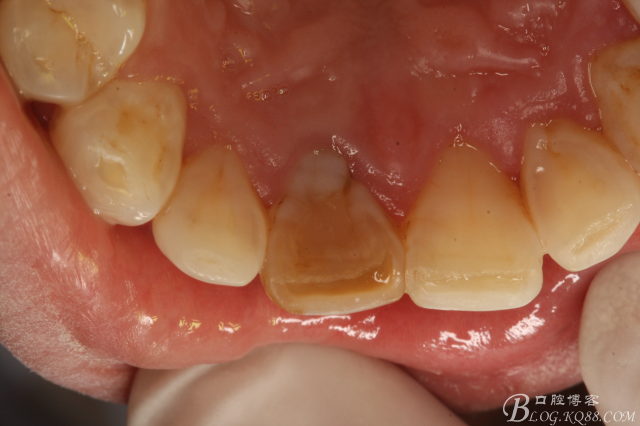

圖1.口內(nèi)像:唇側(cè)粘膜紅腫、牙冠成灰褐色